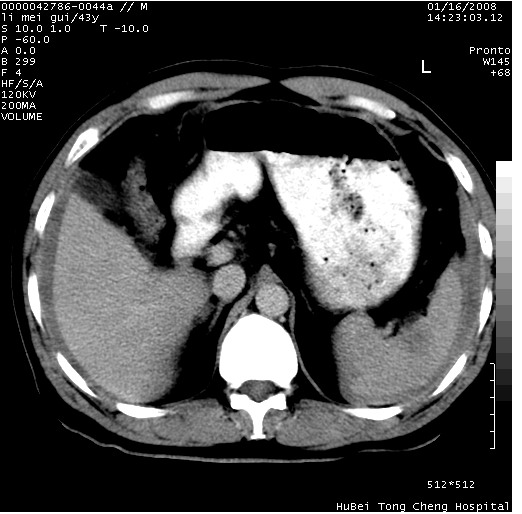

| 患者,男,43岁。突发腹痛2小时,面色苍白,难以平卧。自述近期无明确外伤史,为摩托车驾驶员。 腹部b超检查:脾脏中上极回声异常,肿瘤待排。 临床诊断:腹痛原因待查。 上中腹部ct轴位平扫+增强扫描(层厚10mm,螺距1.0,重建间隔10mm),图像如下: ![]() ![]() ![]() ![]() ![]() ![]() ![]() ![]() ![]() ![]() ![]() ![]() ![]() ![]() ![]() ![]() ![]() ![]() ![]() ![]() ![]() ![]() ![]() ![]() ![]() ![]() ![]() ![]() ![]() ![]() ![]() ![]() ![]() ![]() ![]() zrs发言:支持脾破裂 wwp发言:支持脾破裂并腹水。 xulianj发言:脾脏肿瘤破裂可能性大 zsl6918发言:不像肿瘤出血,考虑还是与外伤后引起的慢性出血有关 zzyy发言:平扫见肝周及脾周积液,脾内密度不均。脾内肿瘤较少见。还是外伤性脾破裂。 沈丘东方医院发言:脾门区一个不均匀强化病灶与其周液体相连多考虑脾占位破裂出血 yixianman001011发言:脾破裂并腹水是可以肯定的,具体原因多以肿瘤性破裂出血,脾脏淋巴瘤可能性大. 结果: 术后,经详细询问患者,其仔细回忆:一月前骑摩托时左侧腰部与别人有“轻微”触碰,因责任在自已,当时又无明显不适,未引起注意。 临床术后诊断:脾破裂并失血性休克(1.外伤性迟发性脾破裂。2.脾脏肿瘤破裂?) 术后标本病检:脾破裂并出血,未见明显肿瘤成份。 原贴地址:http://www.radinet.com.cn/forum_view.asp?forum_id=4&view_id=34070 |